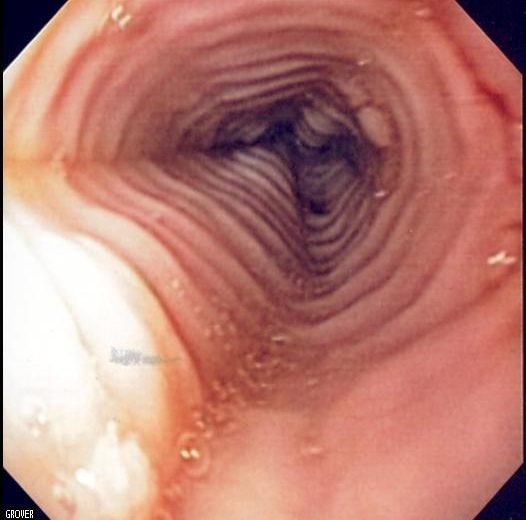

Hoy en día sólo existe una manera de diagnosticar la enfermedad y es realizando una endoscopia digestiva alta con toma de biopsias por el gastroenterólogo. En las biopsias se confirmará la existencia de eosinófilos.